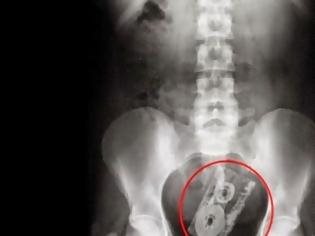

μαγνητικό παιχνίδι

Αυτή η ακτινογραφία απεικονίζει το στομάχι ενός αγοριού το οποίο κατάπινε μαγνητικά κομμάτια από ένα τετράγωνο παιχνίδι ένα τη κάθε φορά. Όταν έφτασαν στο στομάχι του, τα κομμάτια κατάφεραν να επανασυνδεθούν.

ΔΕΝ ΘΑ ΠΙΣΤΕΥΕΤΕ ΣΤΑ ΜΑΤΙΑ ΣΑΣ....Δείτε τι αφαιρούν από το στομάχι ασθενών χειρουργοί! -ΦΩΤΟ - Φωτογραφία 4